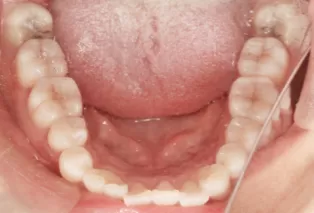

Photos intra-orales après traitement